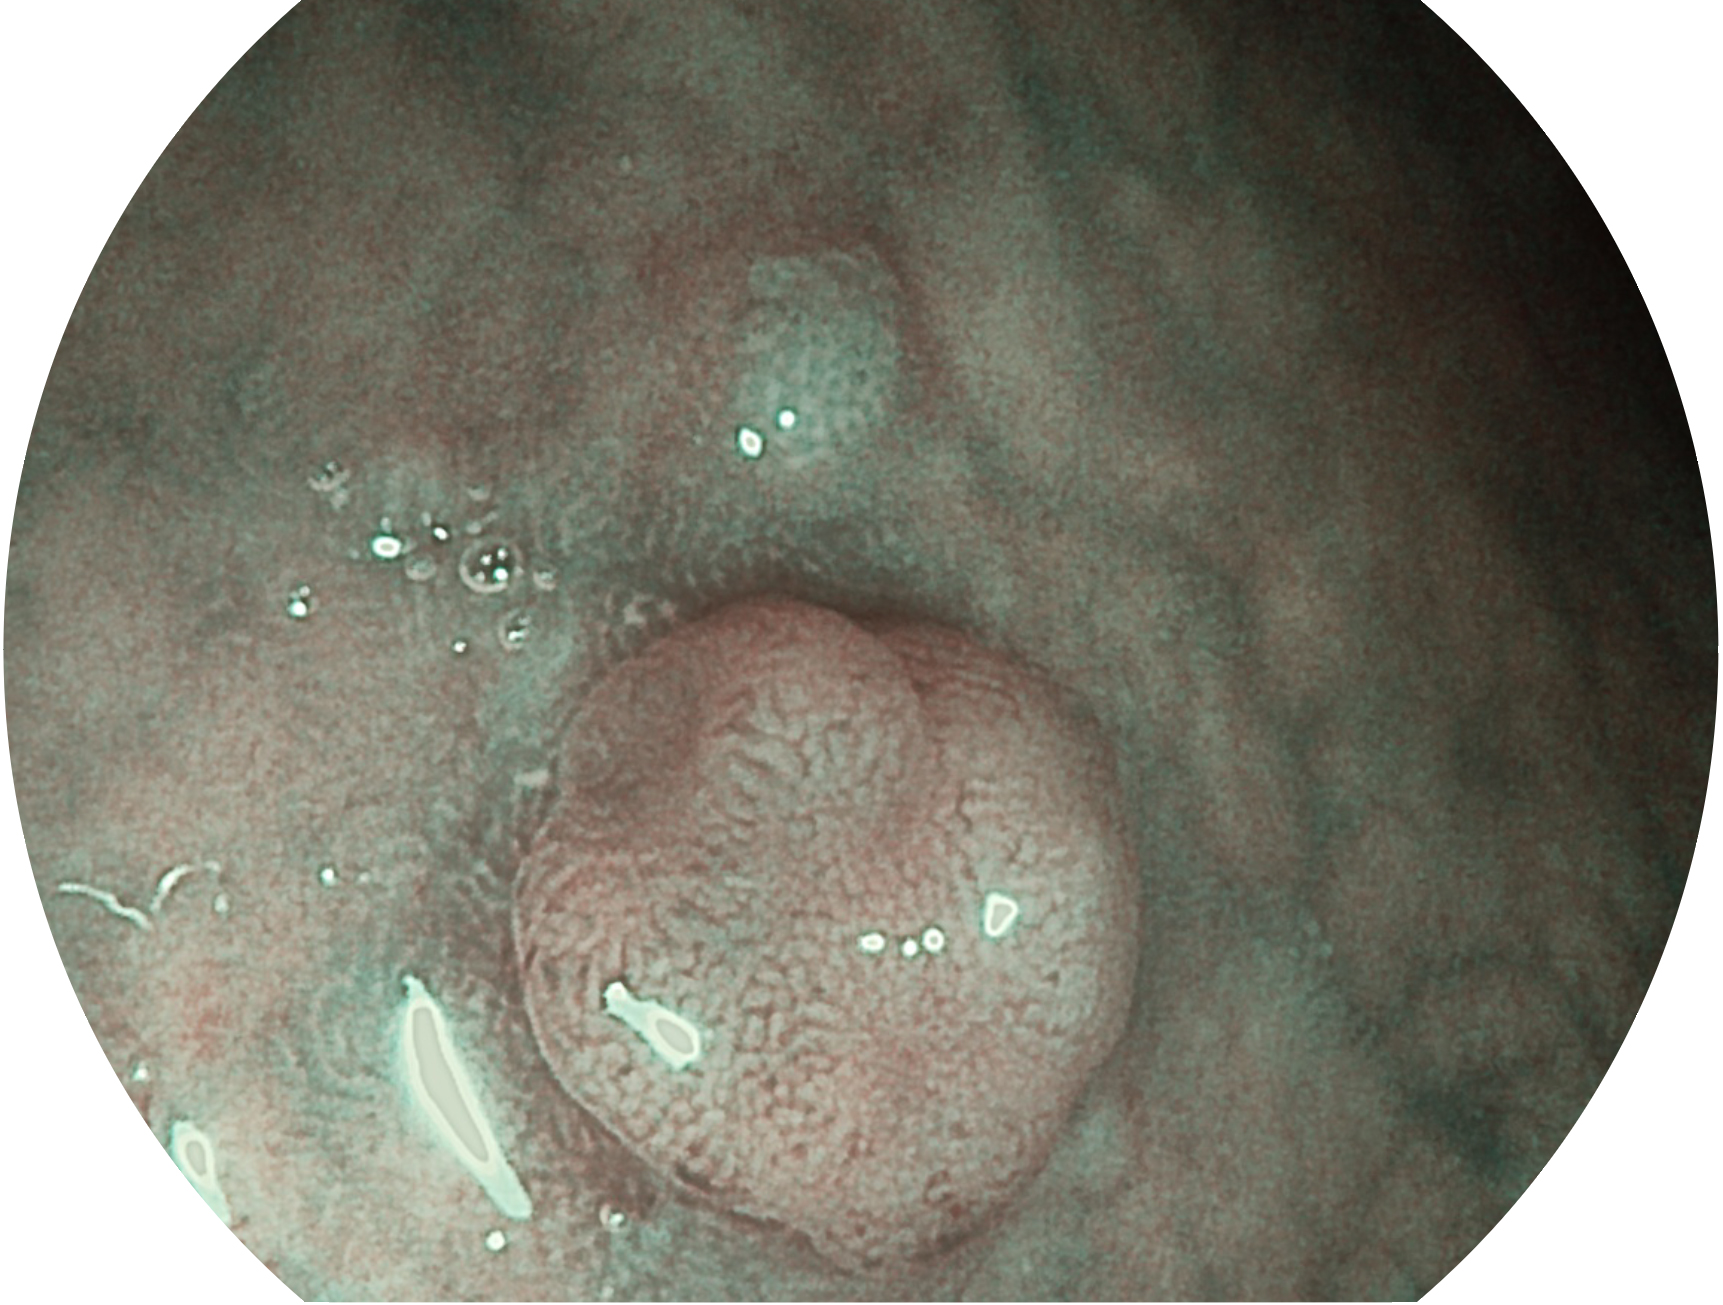

诸侯快讯官网新开发的内镜染色技术,主要是基于多波长LED 光源的开发,VLS-55Q 四波长LED 光源是由四个不同颜色的LED光按照相应照明模式所规定的特定发光比例进行合束后形成,合束后形成的照明光的光谱由红光、绿光、蓝光及蓝紫光这四个不同的波段范围构成。具有更高光谱自由度,通过光谱比例的控制,实现了聚谱成像技术,英文全称为“Spectral Focused Imaging, SFI”,缩写为“SFI”和光电复合染色成像技术,英文全称为“Versatile Intelligent Staining Technology, VIST”,缩写为“VIST”。